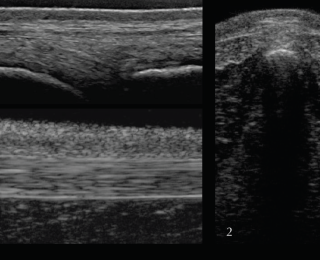

• Ultrasonography of the back should be combined with the radiographic examination and is particularly useful to examine superficial soft-tissue structures and the intervertebral articulations. To assess all structures of interest, both linear and convex transducers are required.

For the supra- and interspinous ligaments (SSL and ISL) longitudinal views are most useful. The images are best acquired with a high-frequency linear transducer using a stand-off pad. The head should be kept in a neutral position as high head carriage may cause relaxation of the SSL and therefore a hypoechogenic appearance. Superficial fibres of the SSL have a horizontal orientation whereas deep fibres of the ISL run in caudoventral direction appearing hypoechogenic in comparison. Care should be taken to position the probe exactly midline at the level of the dorsal spinous processes. The aponeuroses of the epaxial musculature can be imaged off-midline with a parallel fibre pattern similar to the SSL.

In the thoracic (saddle) region the SSL is thin and wide, whereas further caudal in the lumbar region the ligament is thick and narrow with a more echogenic, homogenous appearance. The transverse view of the SSL is less useful due to being more prone to artifacts. In order to achieve the best image quality, the transducer should be tilted cranially and caudally. Published scientific data about the ultrasonographic appearance of the SSL in normal horses and horses with back pain offering information about the potential clinical significance is limited (Henson et al 2007). The clinical significance of heterogenous regions in the SSL should therefore be questioned and further tests, such as diagnostic local anaesthesia, should be applied.

Deep to the ligament the fibrocartilaginous cap, visualised as a hypoechogenic line of approximately 1mm, is visible and runs parallel to the hyperechoic line of the DSP bone surface. The ISS cannot be assessed fully and a statement about potential iminging DSPs should not be made based on ultrasonography alone. The intervertebral articulations can be examined ultrasonographically, both in sagittal and frontal planes, using a convex transducer (Denoix 1999a; Reisinger and Stanek 2005).